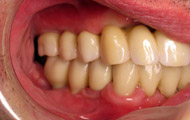

Exemple de 3 dents manquantes remplacées par 3 couronnes sur implants.

Pose des piliers prothétiques et des 3 couronnes scellées.